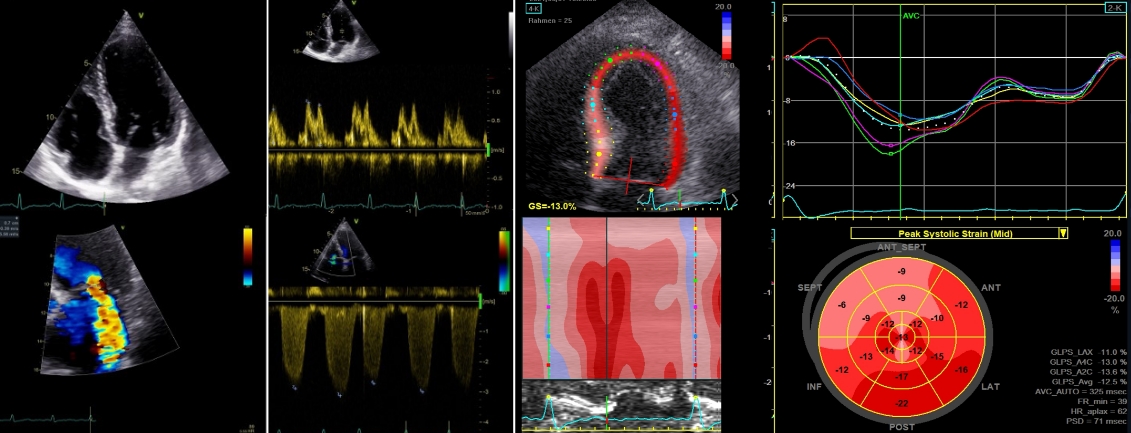

Früherkennung rettet Leben: Mit modernster Diagnostik schaffen wir im Sana Praevention München Schwabing die Grundlage für eine exakte Beurteilung Ihrer Gesundheit. Unser Schwerpunkt liegt auf hochauflösender Bildgebung wie Ganzkörper-MRT und Herz-CT, die auch kleinste Veränderungen sichtbar machen – lange bevor Symptome auftreten. So lassen sich Herz-Kreislauf-Erkrankungen, Tumoren oder andere Risiken frühzeitig erkennen und gezielt behandeln.

Dank der Kombination aus innovativer Medizintechnik, umfassender Laboranalytik und individueller ärztlicher Beratung erhalten Sie ein detailliertes Gesundheitsprofil. Dieses Wissen gibt Ihnen Klarheit und ermöglicht, gemeinsam mit unserem Team präzise Präventionsstrategien zu entwickeln.